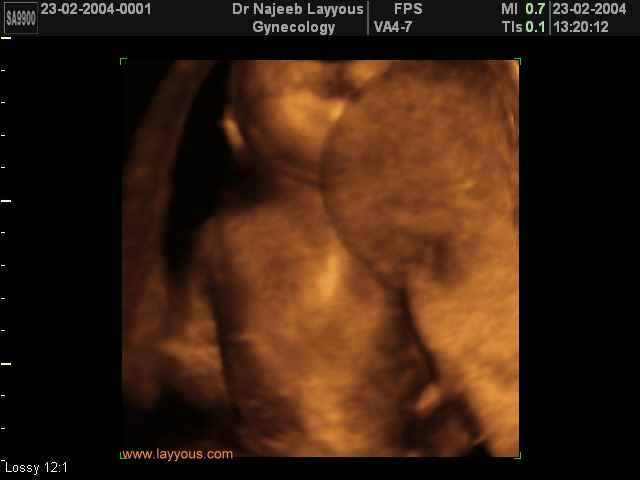

3D Photos échographie des parties du fœtus | Dr N Layyous

3D Photos échographie des parties du fœtus